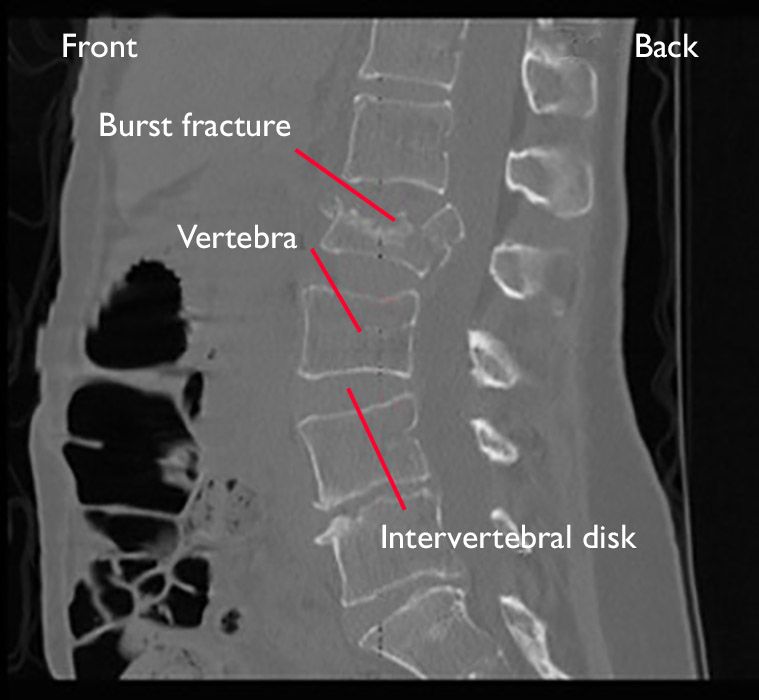

A compression fracture occurs when part of a vertebra, or bone in the spine, collapses. Mri Of Lumbar Spine History Of Fall With Back Pain Radiate To Leg Rule Out Spinal Stenosis Impression Burst Fracture Of L2 Stock Image Image Of Lumbar Backbone 184876849

A t12 or l1 compression fracture most commonly happens as a wedge fracture, which occurs when the front part of the vertebra collapses and the back doesn't, . A compression fracture is a type of fracture, or broken bone that affects your vertebrae, the bones in your back. Most of the time, the anterior, . The bones of the spine have two main section. Spinal fractures or a dislocation of one or more vertebrae in a spine caused by trauma is considered a serious orthopedic injury. This type of fracture occurs when one or more vertebrae—the bones that comprise the spine—breaks and collapses. Spondylolysis is a spinal fracture of a bone structure called the pars interarticularis, which connects the facet joints of the spine. Spinal fractures are different than a broken arm or leg, a fracture or dislocation of a vertebra can cause bone fragments to pinch and damage the spinal .